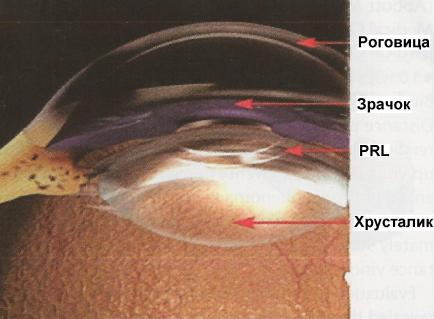

- Заднекамерные — фиксируются между радужкой и хрусталиком.

Интраокулярные линзы устанавливаются внутрь глаза с сохранением хрусталика. При этом пациент приобретает максимально возможное зрение без дополнительной коррекции, поскольку фокусировка изображения осуществляется непосредственно на сетчатку.

Операция по имплантации линз проходит под местной анестезией и длится около 10-15 минут. Оптические изделия достаточно хорошо фиксируются и занимают стабильное положение, поэтому нисколько не влияют на структуру глаза и не ощущаются в процессе эксплуатации. ФИОЛ устанавливаются через тоннельный роговичный разрез, диаметр которого составляет 2.7 мм. Впоследствии контактные линзы самостоятельно герметизируются, а потому не требуют наложения швов.